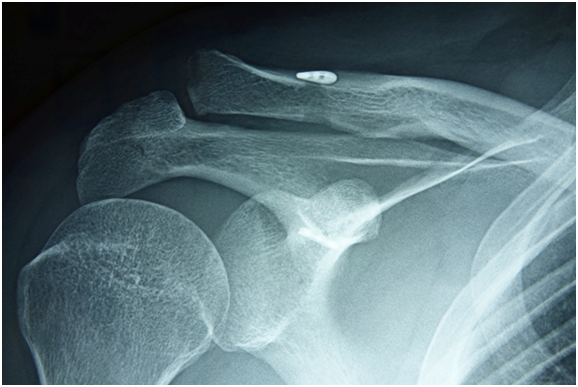

At final follow-up, no patient displaced to the preoperative state. Thirteen (52%) patients displaced to a grade II level (Rockwood classification3). These patients averaged 10 days (4-16 days) from the date of injury to the date of surgery. (Figure 3 & Table 1) Eight (32%) of the 25 had displaced back to a grade III level (Rockwood classification3). These patients averaged 18 days (6-38 days) from the date of injury until date of surgery (Figure 4 & Table 1).

Figure 4 Grade III loss of reduction, 24 weeks after surgery.